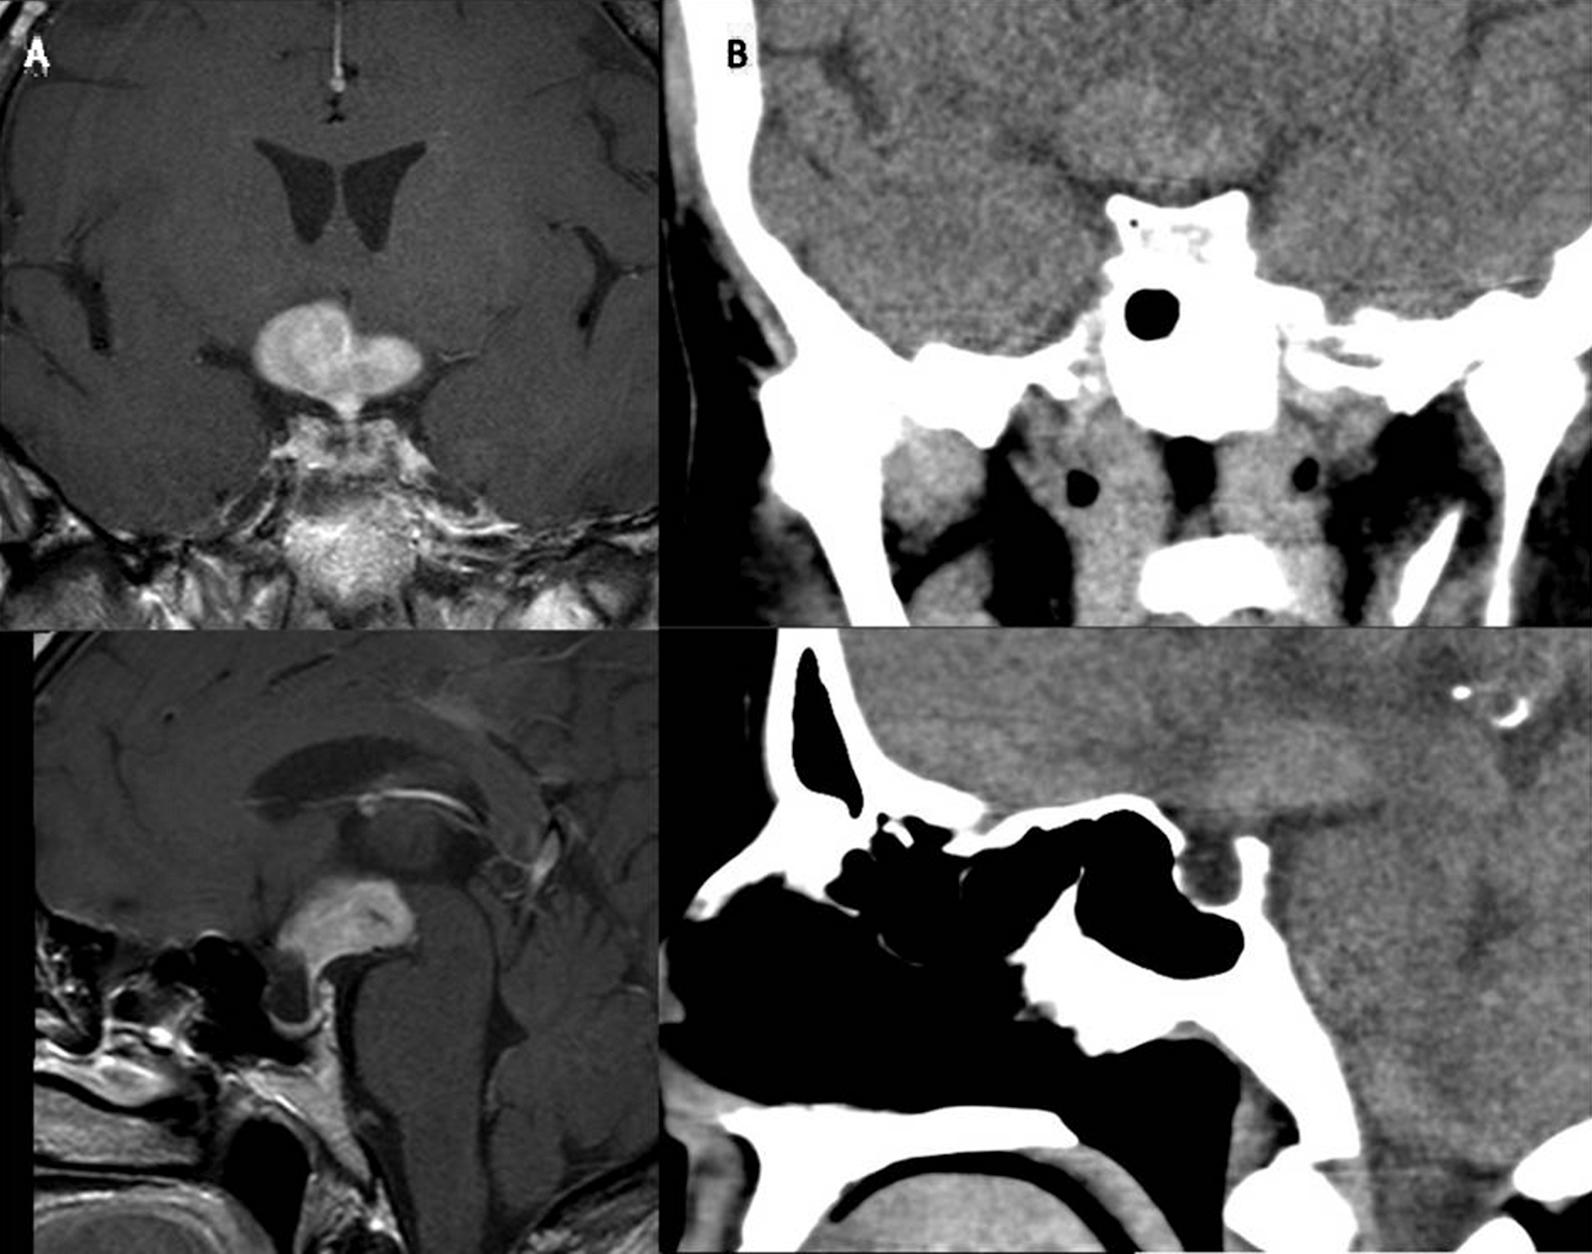

We report the case of a 48-year-old Caucasian woman with progressive short-term memory deterioration, headache, mental confusion, diabetes insipidus (DI) and hypopituitarism. Early findings were suggestive of a pituitary apoplexy. The results of tests performed during the initial admission at the tertiary health center revealed hypernatremia, hypopituitarism and DI. Intravenous hydrocortisone treatment was initiated for the secondary adrenal insufficiency, and 75 mcg/day of levothyroxine was started for the secondary hypothyroidism on the fourth day following hydrocortisone treatment. A daily dose of 120 mg desmopressin melt tablet was started twice a day for polyuria/polydipsia after the patient's volume status was balanced. A brain magnetic resonance imaging scan revealed a mass lesion in the hypothalamic area, which was surrounded by marked edema. Anti-edema treatment was initially started considering the suggestion by our neurosurgery team. The patient's clinical and laboratory findings improved after the initiation of the anti-edema therapy. Afterwards, a biopsy was performed, which diagnosed a malignant diffuse large B-cell lymphoma. Subsequently, intravenous high-dose methotrexate-based therapy was started; however, after the second cycle of chemotherapy, the patient died due to sepsis.

我们报告了一例 48 岁白人女性,表现为进行性短期记忆恶化、头痛、精神错乱、尿崩症(DI)和垂体功能减退。早期发现提示垂体卒中。在三级保健中心初次入院期间进行的检查结果显示高钠血症、垂体功能减退和 DI。为继发性肾上腺功能不全开始静脉注射氢化可的松治疗,在氢化可的松治疗后第 4 天开始每天 75mcg 左甲状腺素治疗继发性甲状腺功能减退。在患者的容量状态平衡后,开始每天两次服用 120mg 去氨加压素片治疗多尿/多饮。脑磁共振成像扫描显示下丘脑区域有一个肿块病变,周围有明显的水肿。考虑到我们神经外科团队的建议,最初开始了抗水肿治疗。抗水肿治疗开始后,患者的临床和实验室检查结果有所改善。随后进行了活检,诊断为恶性弥漫性大 B 细胞淋巴瘤。随后,开始了静脉注射大剂量甲氨蝶呤为基础的治疗;然而,在第二个化疗周期后,患者因脓毒症死亡。